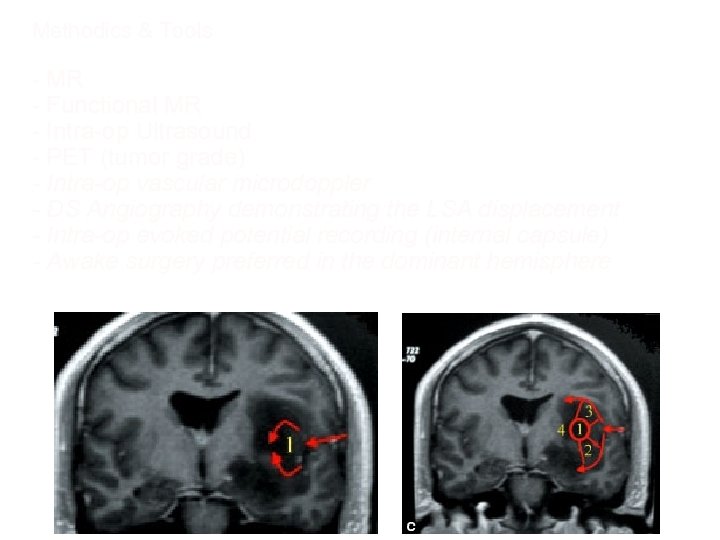

Methodics & Tools - MR - Functional MR - Intra-op Ultrasound - PET (tumor grade) - Intra-op vascular microdoppler - DS Angiography demonstrating the LSA displacement - Intra-op evoked potential recording (internal capsule) - Awake surgery preferred in the dominant hemisphere

Tumor LSAs medial displacement Open biopsy: anaplastic glioma Anaplastic Astrocytoma: atypia, ipercellularity and mitosis (WHO III)